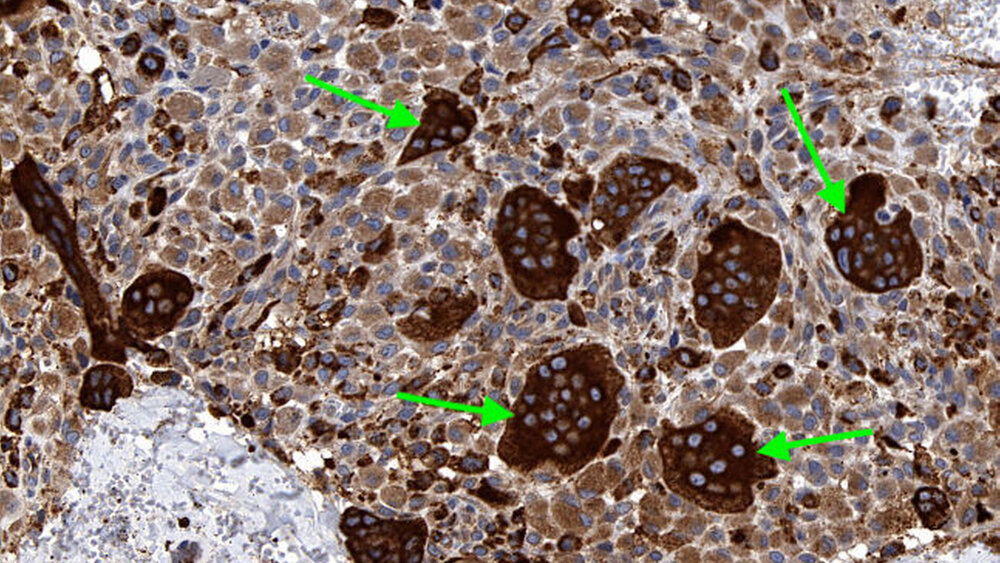

Zufallsbefund eines Riesenzelltumors bei langjähriger Bruxismus-Patientin